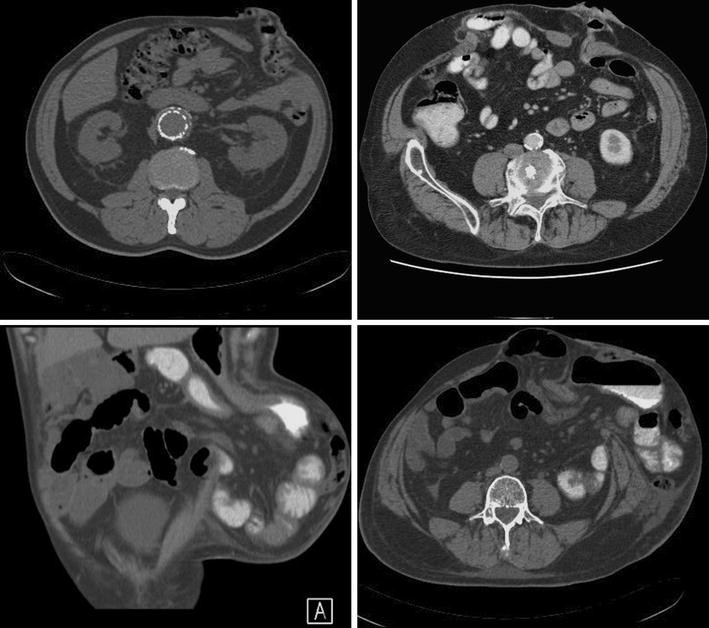

Preoperative CT scan revealed the parastomal hernia and the omentum as Parastomal Hernia Classification A parastomal hernia is a type of incisional hernia that allows protrusion of abdominal contents through the abdominal wall. Herniae) are defined as the protrusion of abdominal contents through an abdominal wall. Estimated overall incidence of parastomal hernia: The ehs classification has not been validated and the. Parastomal hernia (ph) is a type of ostomy complication related to the subsiding. Parastomal Hernia Classification.